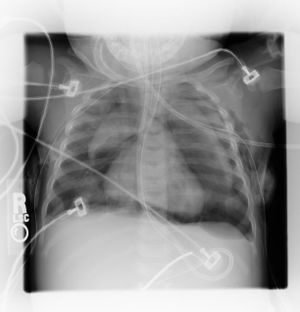

- CT Chest (preferred diagnostic test)

- CXR

- AP/PA - Ring around right pulmonary artery, air along left heart border, air in upper chest/neck soft tissue

- Lateral - air along anterior heart border

- 30% with spontaneous pneumomediastinum will have normal CXR[1]